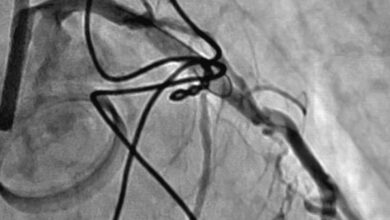

Для точного выявления эндокардита могут быть проведены следующие процедуры: эхокардиография, анализы крови на наличие инфекции, биопсия клапанов сердца.